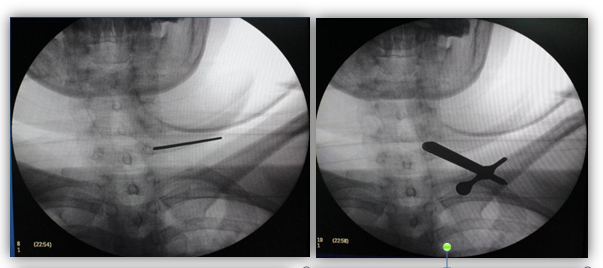

1. 麻醉成功后定位,置入通道

2. 镜下操作

3. 摘除髓核后

4. 术后患者症状即刻缓解